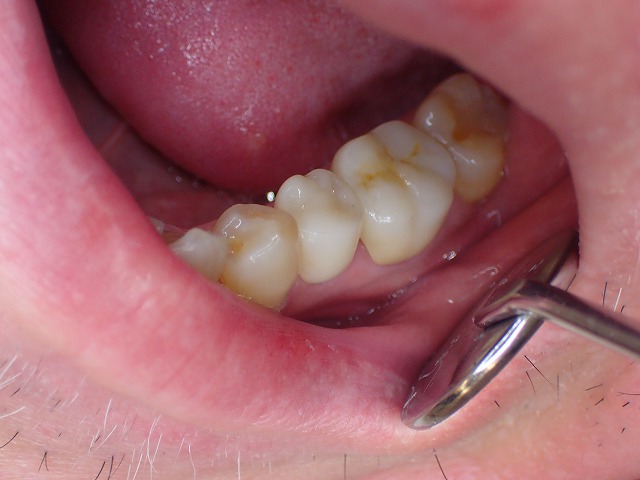

ジルコニアセラミック装着

無事にジルコニアクラウンになりました。

これでCAD/CAM冠のトラブルからは

逃避できるでしょう。